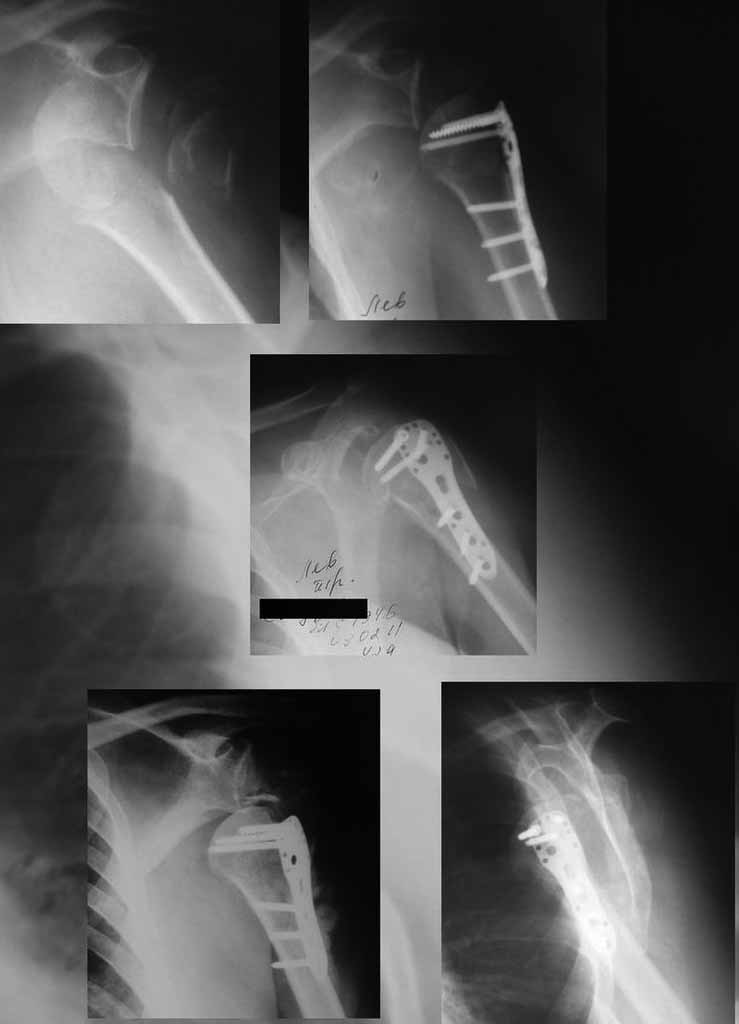

Здесь результат похожего случая, больная 87 лет, отягощенная сердечными делами и два года назад установка pacemaker и нескольких стентов. На третий день, сегодня утром сделали операцию. Послеоперационный псевдовывих связанный с релаксацией мышц и общим обезболиванием.

Для адекватного лечения необходимо знать состояние костного компонента - нужно КТ с артрографией что поможет частично оценить состояние сухожилий и лабриум. Уже по снимку можно сказать что существует большой костный дефект в задне-наружном сегменте.

Если говорить об оперативном лечении, то о протезировании можно думать если существует артроз или некроз головки плеча, в данной ситуации я бы воздержался от протезирования из за нестабильности, если хорошо сохранен делтоид то может быть реверсионный протез который более стабильный. Другой вариант восстановление мягких тканей и тут я полностью согласен с Олегом что

нужно адекватное восстановление манжетки и восстановление пассивной стабильности сустава путем подшивания капсулы (Банкарт) натяжение капсул, возможно транспозиция кораковидного отростка если есть отломана передняя часть гленоидум или другая техника в зависимомти от результата КТ и операционных находок.

В послеоперационном периоде потребуется фиксация руки в течении 1,5 месяцев и длительная поэтапная разработка иногда в течение 1-1,5 лет.